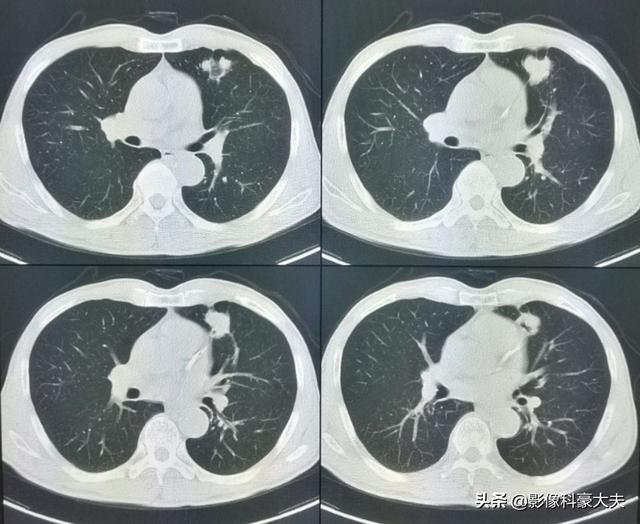

Dieser unregelmäßige Knoten in der linken Lunge ist der Primärherd, der nur 2,6 cm groß ist. Lungenkrebs mit Knochenmetastasen wie diesem ist nicht mehr operabel. Man kann ihm nicht helfen, Lungenkrebs ist zu häufig und einige der frühen Symptome sind atypisch oder sogar symptomlos.Bei etwa 30 % der Lungenkrebse sind Symptome von Metastasen die erste Manifestation, und Metastasen werden zuerst entdeckt, bevor weiterer Lungenkrebs entdeckt wird.

Gerade vor ein paar Tagen nur einen Fall von Lungenkrebs Knochenmetastasen Patienten diagnostiziert, ist sein Symptom langfristige lumbale Rückenschmerzen, haben sie immer gedacht, dass es lumbale Muskelzerrung ist, oder von lumbalen Bandscheibenvorfall leiden, kümmerte sich nicht, wirklich der Schmerz ist ernst, und erschien die Nervensymptome der unteren Gliedmaßen, nur in das Krankenhaus für die Prüfung, gegeben, um seine CT-Untersuchung, festgestellt, dass es offensichtlich Wirbelknochen Zerstörung sind ...... detaillierte Verfolgung der Krankengeschichte, festgestellt, dass der Patient seit langem Hustensymptome hat, so hoch Verdacht auf Lungenkrebs Knochenmetastasen, die Lunge CT-Untersuchung, fand der primäre Fokus ...... eine große Lungenkrebs.